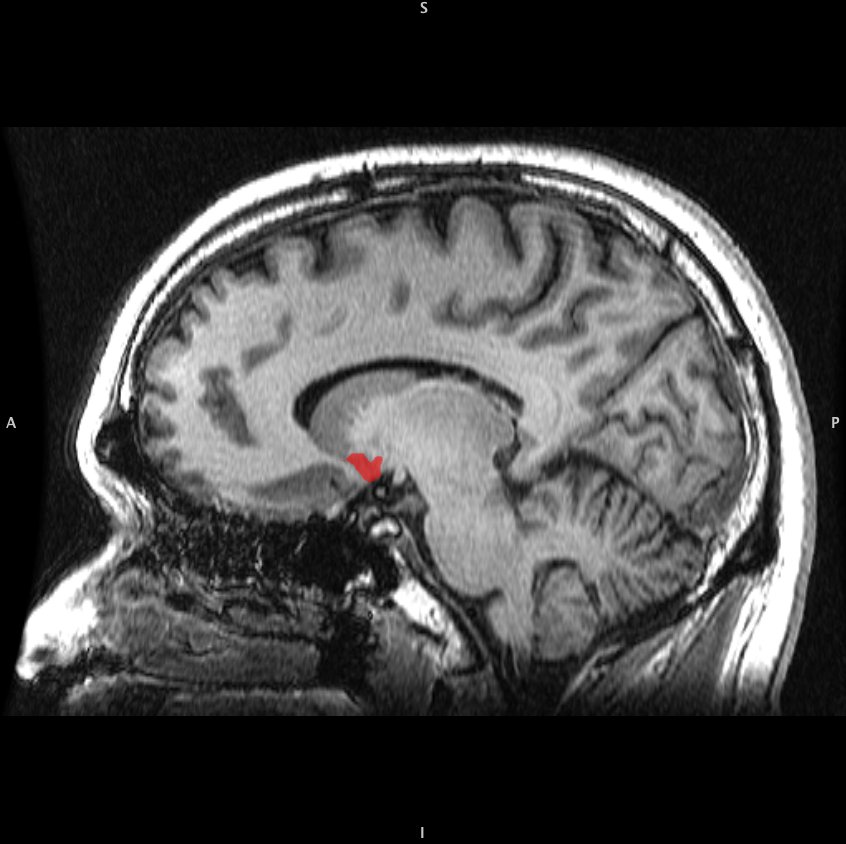

The most commonly cited brain region when discussing pleasure is the nucleus accumbens. This small subcortical structure is a critical part of what is commonly referred to as the “reward system” in the brain. The nucleus accumbens receives a high density of projections from the ventral tegmental area (VTA) neurons. These neurons produce dopamine, which is the neurotransmitter generally associated with the creation of pleasurable or rewarding feelings (Pierce and Kumaresan, 2006). The nucleus accumbens and VTA are just two parts of the limbic system, which plays a critical role in emotion and motivation.

The brain region most associated with sexual pleasure, particularly orgasm, is the orbitofrontal cortex. The orbitofrontal cortex has been associated with conscious control of actions, and hyperactivity of the area has been found in patients with obsessive-compulsive disorder (Beauregard et. al., 2001). A decrease in blood flow has been found during both male and female orgasm, possibly indicating a decrease in activity and a loss of “active control”. (Georgiadis et. al. 2006). The activity of the orbitofrontal cortex has also been found to be modulated by pleasure induced by other stimuli, such as food and music (Georgiadis and Kringelbach, 2012). Hopefully as the topic of sex becomes more commonly discussed and neuroimaging techniques develop, we can learn even more about this most crucial of human behaviors.